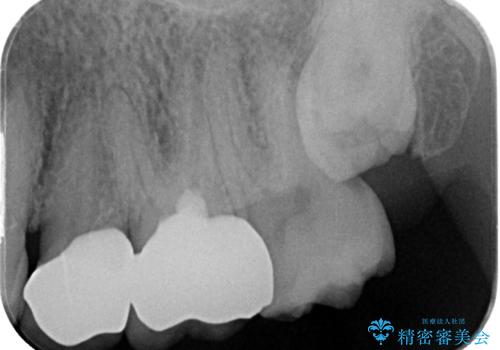

- 「奥歯がたまにしみるときがある」との主訴で来院された患者様です。

検査の結果、虫歯が非常に深く、通常であれば神経をすべて取り除く抜髄処置が必要な状態でした。

神経をすべて取り除いてしまうと歯の寿命が縮まってしまうため、感染している神経の一部を取り除く生活歯髄療法を行っていくことご提案しました。

生活歯髄療法を行い状態が安定していることを確認してからオールセラミッククラウンによる補綴治療を手前の銀歯を含め2本同時に行いました。